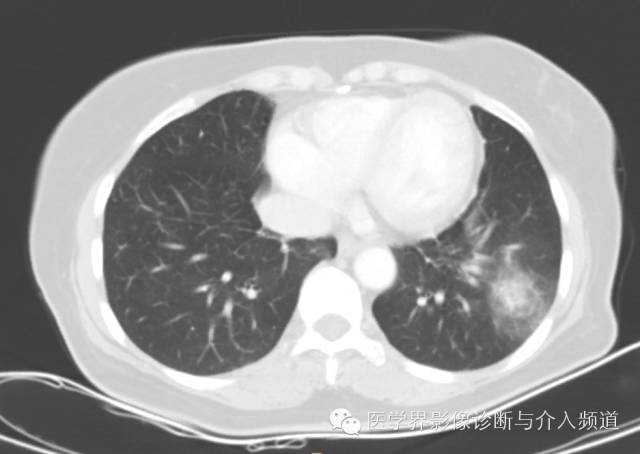

左肺下叶可见软组织密度肿块影,形态不规则,边界不光整,与胸膜粘连不清,周围肺组织呈磨玻璃密度改变,病变内部不均匀强化,低密度区不强化。

病变部位:右肺下叶居多,既可位于中央区,也可位于周围带,靠近胸膜,极少数位于叶间裂。

病变大小:病变大多数体积较小,直径小于4 cm,也有个别病变体积较大。

综上,若女性,发现肺内单发圆形或类圆形肿块,边界光整,内部看见囊变,若还有空气新月征、晕征、周围肺组织肺气肿、钙化,增强扫描明显均匀强化,应考虑硬化性血管瘤的可能。